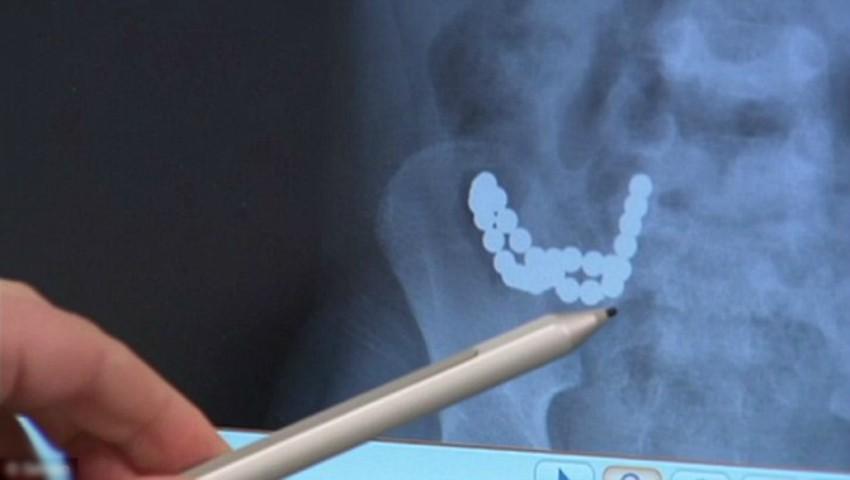

Un băiețel de doar 5 ani, din Melbourne, Australia, a înghițit 30 de magneți de frigider și le-a dat mari bătăi de cap medicilor. Radiografia i-a lăsat pe medici fără cuvinte.

Mama copilului s-a declarat șocată că și-a găsit fiul făcut ghem de durere. Băiețelul nu și-a pierdut viața în urma incdentului. Medicii chirurgi au stat în operație 6 ore pentru a-i scoate magneții, care i se încolăciseră în jurul stomacului.Unul dintre doctori a spus că nu a mai pomenit așa ceva. Potrivit declarațiilor sale, intervenția de îndepărtare a magneților a fost foarte dificilă, întrucât aceștia i-au perforat stomacul, plus că au fost nevoiți să îi taie și o bucată din intestin.sursa